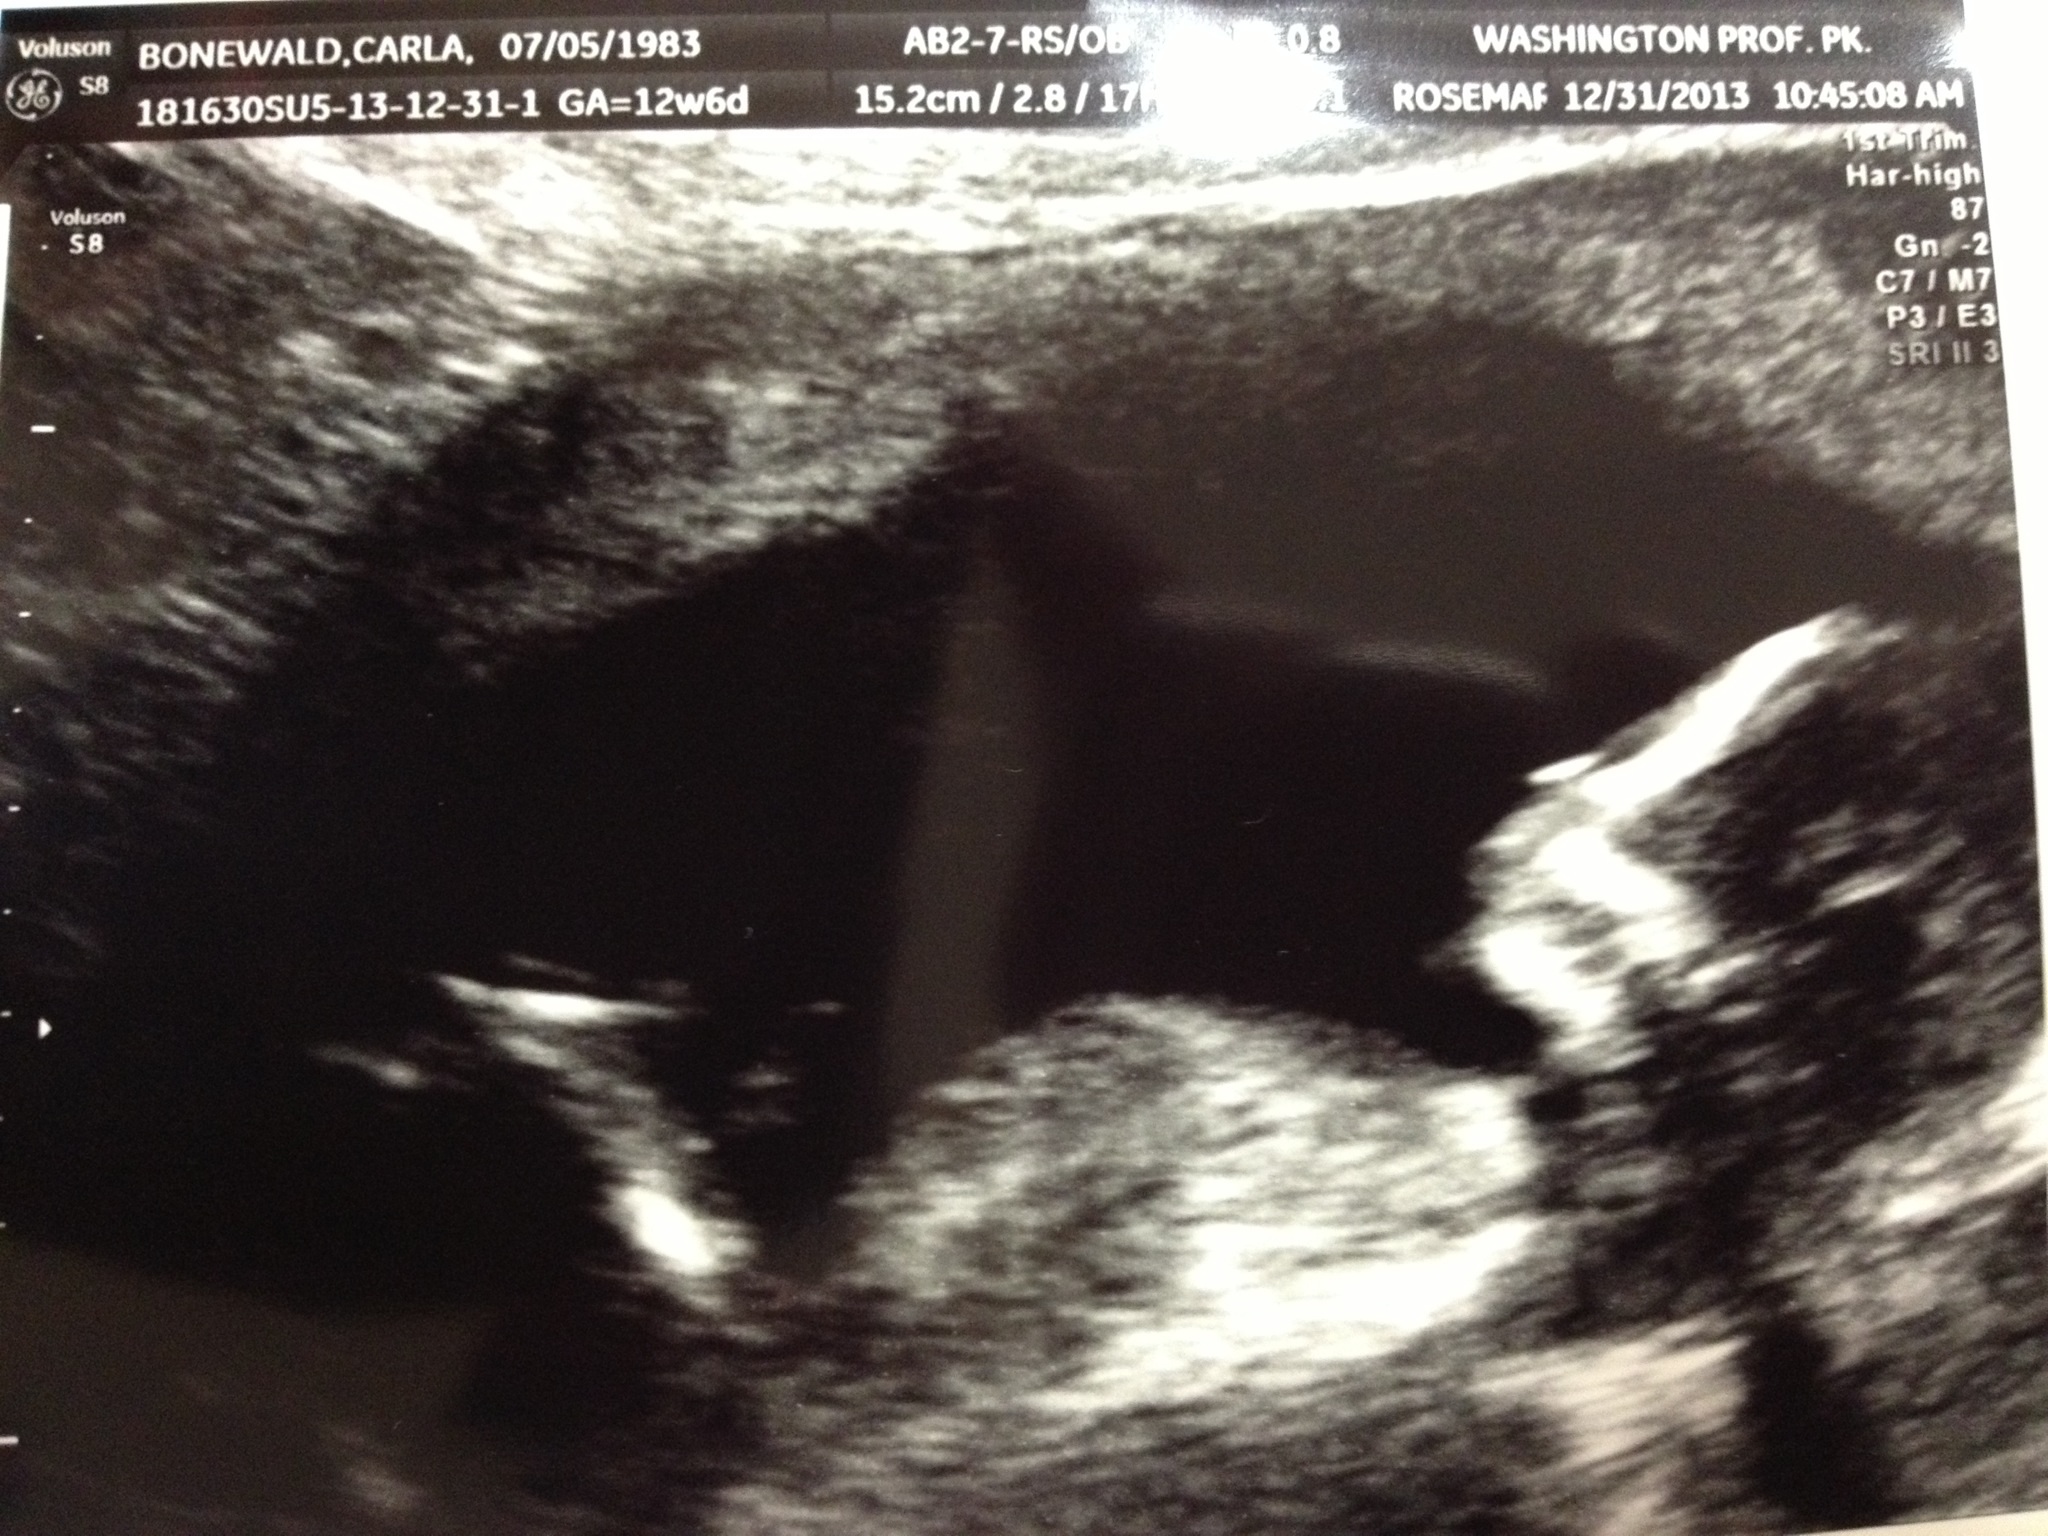

I am going to guess girl. Congratulations new mama!

Can't really see anything. GL!